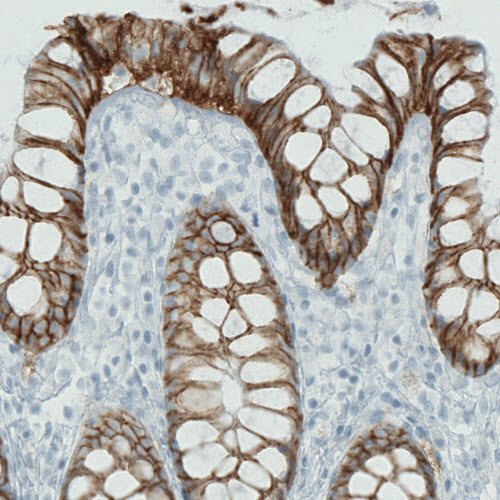

Immunohistochemical staining of human kidney shows strong membranous immunoreactivity in renal tubules, but not glomeruli.